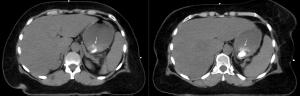

A 57-year-old woman with a history of stage IIB breast cancer (ypT2N1M0) status post neoadjuvant chemotherapy and left partial mastectomy presents to the radiation oncology clinic for CT simulation in preparation for breast radiotherapy. Noncontrast CT scan incidentally found the abnormality depicted with arrows below. What is your diagnosis?